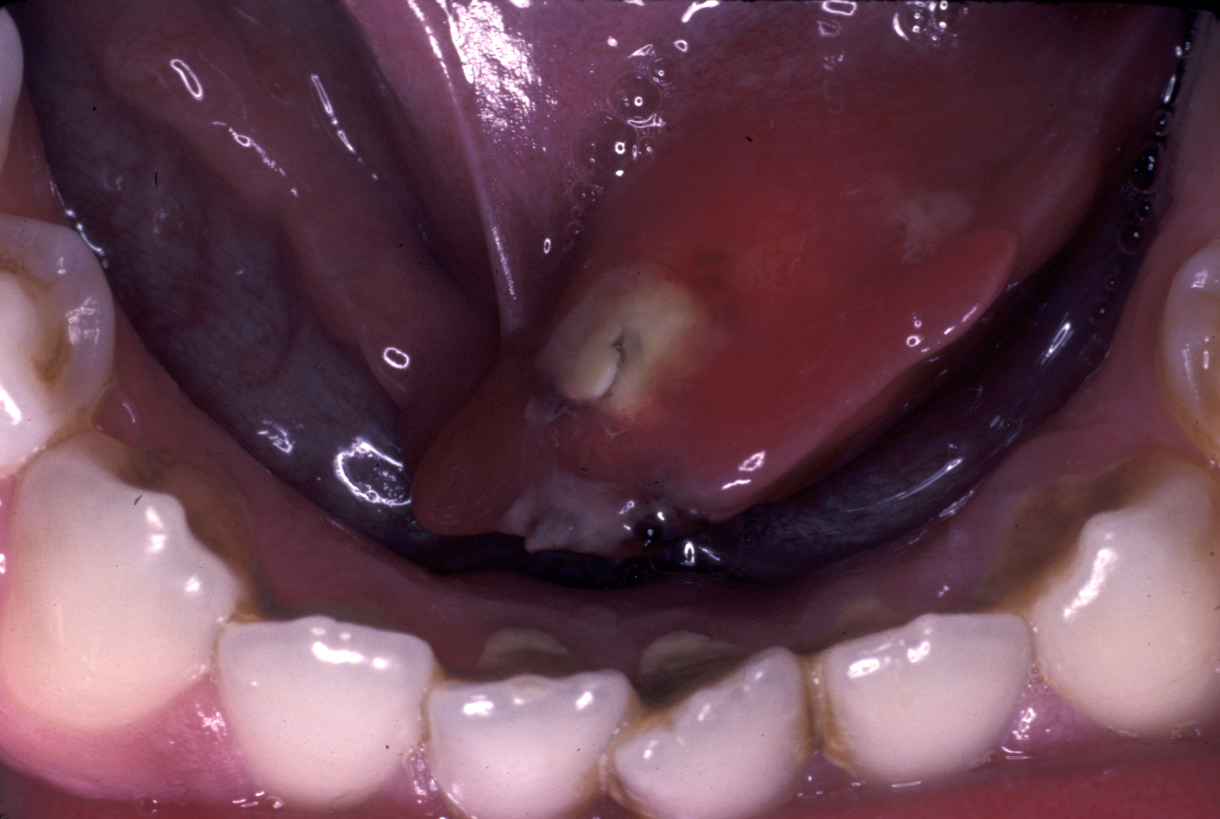

Now relatively rare, this condition usually affects the parotid gland. It is microbiologically different from infected obstructive sialadenitis (usually seen in the submandibular gland (see above) but also parotid). Classically it occurred in postoperative patients who were dehydrated. It still occurs in older patients who are dehydrated and debilitated but underlying Sjögren’s syndrome (see below) nowadays is a more frequent cause. There will be a swollen, erythematous (red skin), painful gland, often accompanied by systemic malaise (see Figure 4). Staphylococcus aureus is the usual organism, streptococci and other anaerobic bacteria are also frequently cultured.

Figure 4: Patient with bacterial sialadenitis. These patients can become very unwell.

Pus may be discharging from the papilla (see Figure 5). If not, the gland should be milked to obtain pus for microbiology. Abscess formation may be a (rare) sequela (develop as a consequence of the initial condition).

Figure 5: Pus discharging at the parotid duct.